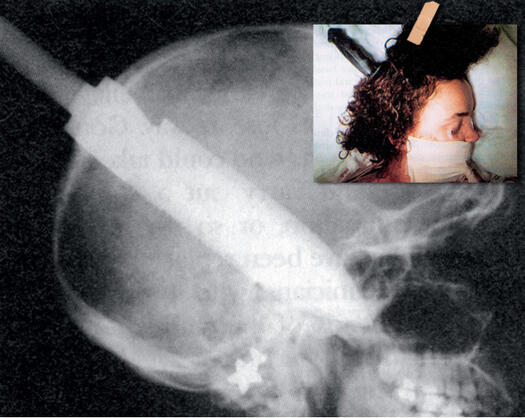

ЕКСПОНАТ 10

Нож

Скапан маниак се прокрадва в метрото зад 22-годишната жена. Жената останала в съзнание през цялото време до болницата. Лекарите успяват да ѝ спасят живота. Съвсем леко е пострадало периферното зрение.